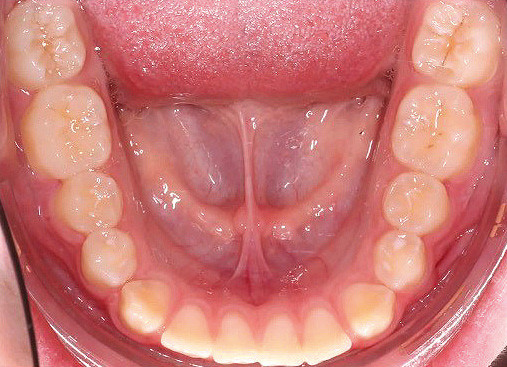

Klinisches Fallbeispiel 2 (Abb. 2a–y)

Distalbiss und tiefer Biss bei einem zwölfjährigen Mädchen. Die Behandlung erfolgte mit Invisalign und Precision Wings. Insgesamt waren zwei Schienensätze notwendig. Die Gesamtbehandlung dauerte 18 Monate.Bei der Planung des ClinCheck wurde der tiefe Biss vorwiegend über eine Intrusion der Unterkieferfront behoben, um die Lachlinie der Patientin nicht negativ zu beeinflussen. Die Oberkieferfront wurde nur retrudiert, jedoch vertikal nicht intrudiert. Während der Phase des Mandibular Advancement wurde die Wirkung der Precision Wings durch den Einsatz von Klasse II-Gummizügen unterstützt. Schlussendlich wurde auch der hängenden Okklusionsebene durch eine einseitige Intrusion der Molaren im ersten Quadranten Rechnung getragen.